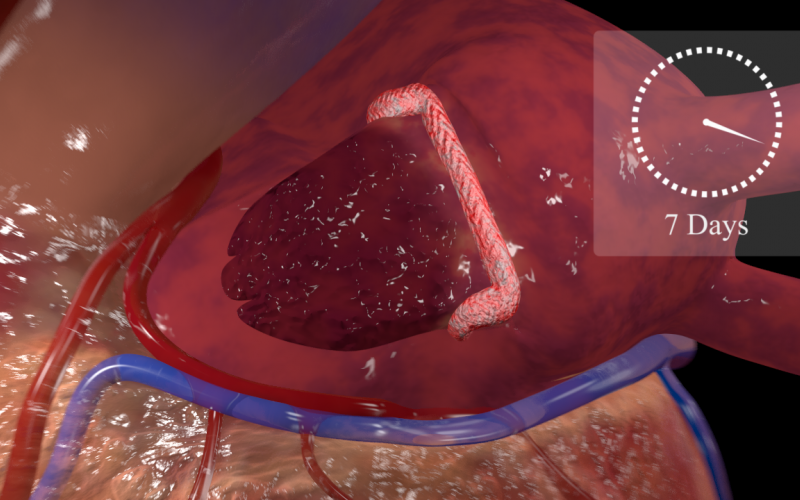

Left arterial appendage shown 7 days after an Atriclip has been placed, but prior to complete atrophy and necrosis.